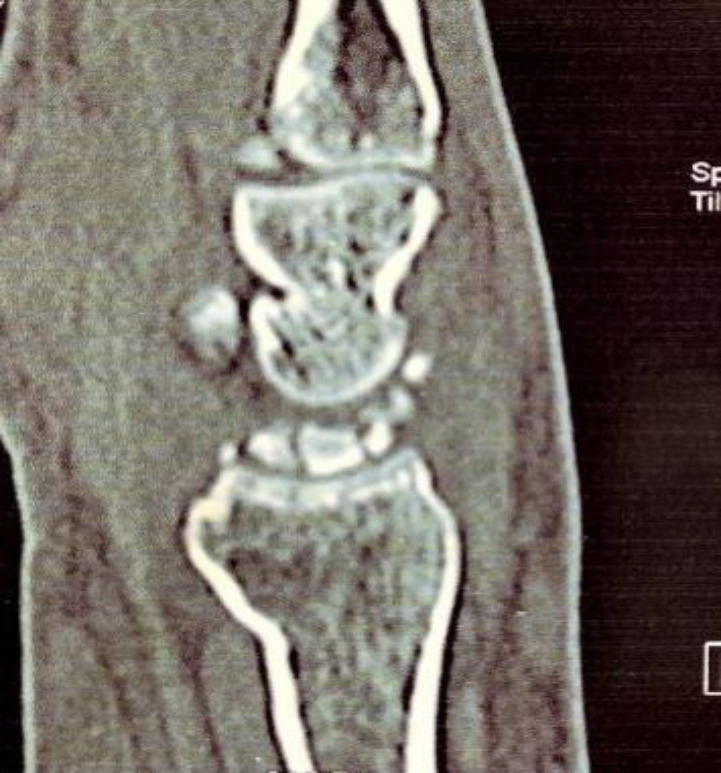

Abstract Image